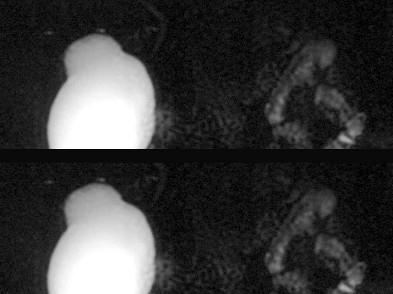

问题 女,31岁,右侧腰部胀痛不适,MRI检查如图所示,下列说法正确的是 ( )

选项 A、左肾输尿管未见异常 B、考虑为右侧输尿管囊肿 C、右侧输尿管粗细不均并迂曲扩张 D、右侧输尿管下段呈囊样扩张 E、右肾重度积水

答案 ABCDE